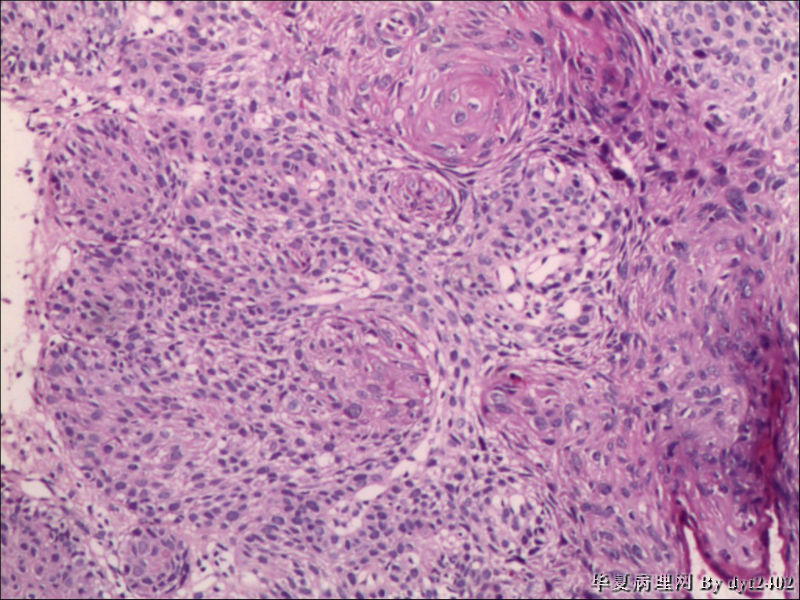

• 宫颈活检 其中一点较迷糊图1

图1

四点中三点是CIN iii,另一点怀疑有更重病变

这个病人是44岁,去年11月底阴道脱落细胞、TCT均见细胞异常,建议活检,病人犹豫,接着单位组织到外院体检时做阴道镜正常,后霉菌感染,此时宫颈未涂醋肉眼看还光滑,直至今年3月来做活检,事前做白带检查又见异常细胞,宫颈未涂醋见后上唇白上皮,涂醋酸后上下唇都有厚白上皮,镶嵌,夹活时上皮剥脱,未能夹到间质,阴道镜医生说至少有CIN III 到原位癌了。。镜下其中3点CIN III无疑,唯有9点处如6、7、11、14等所示结构,但我未见间质浸润,不能说是浸润癌,不知道有没基底细胞样鳞癌的可能,我发了个原位癌不除外深部有更重病变,。